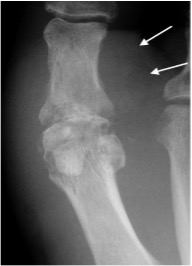

Gout

- Hyperuricaemia causes deposition of urate crystals

- First metatarso-phalangeal joint is commonly involved, termed a podagra

- Well-defined erosions with sclerotic borders which have a ‘punched out’ or ‘rat bite’ appearance and overhanging margin

- Joint space and bone density are preserved until late in the course of the disease

- Urate crystals deposited in the soft tissues form tophi and periarticular lobulated soft tissue masses

- Chondrocalcinosis may represent deposition of calcium pyrophosphate dihydrate (CPPD) crystals (pseudogout)

Gout of first MTP joint with well defined ‘punched out’ erosion with overhanging margin (arrow) and soft tissue swelling (arrowheads)